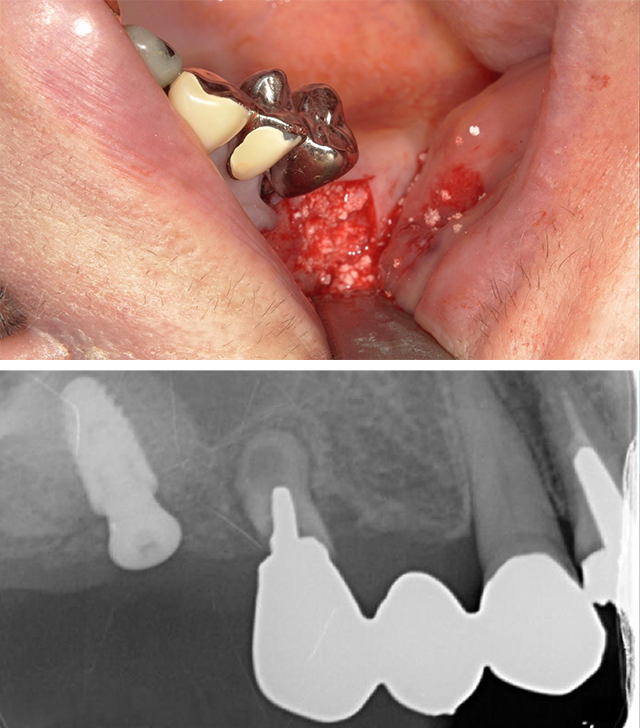

志賀先生は骨不足や粘膜薄い症例に対して、どの症例でどの補助手技(GBR、サイナスリフトなど)を使用すべきか、その選択基準を明確に解説します。

「難しい症例には手を出さない」という選択肢ではなく、どの症例にどの手技を使うべきかを学び、確実に治療を成功させる自信をつけることができます。

付着歯肉が確保できる場合は1回法で、付着歯肉がない場合は2回法になりますがメスの入れ方(舌側寄りに切開線を引いてあげる)でも付着歯肉を温存することも可能です。

また1回法後に2回法へ切り替える方法についても説明します。